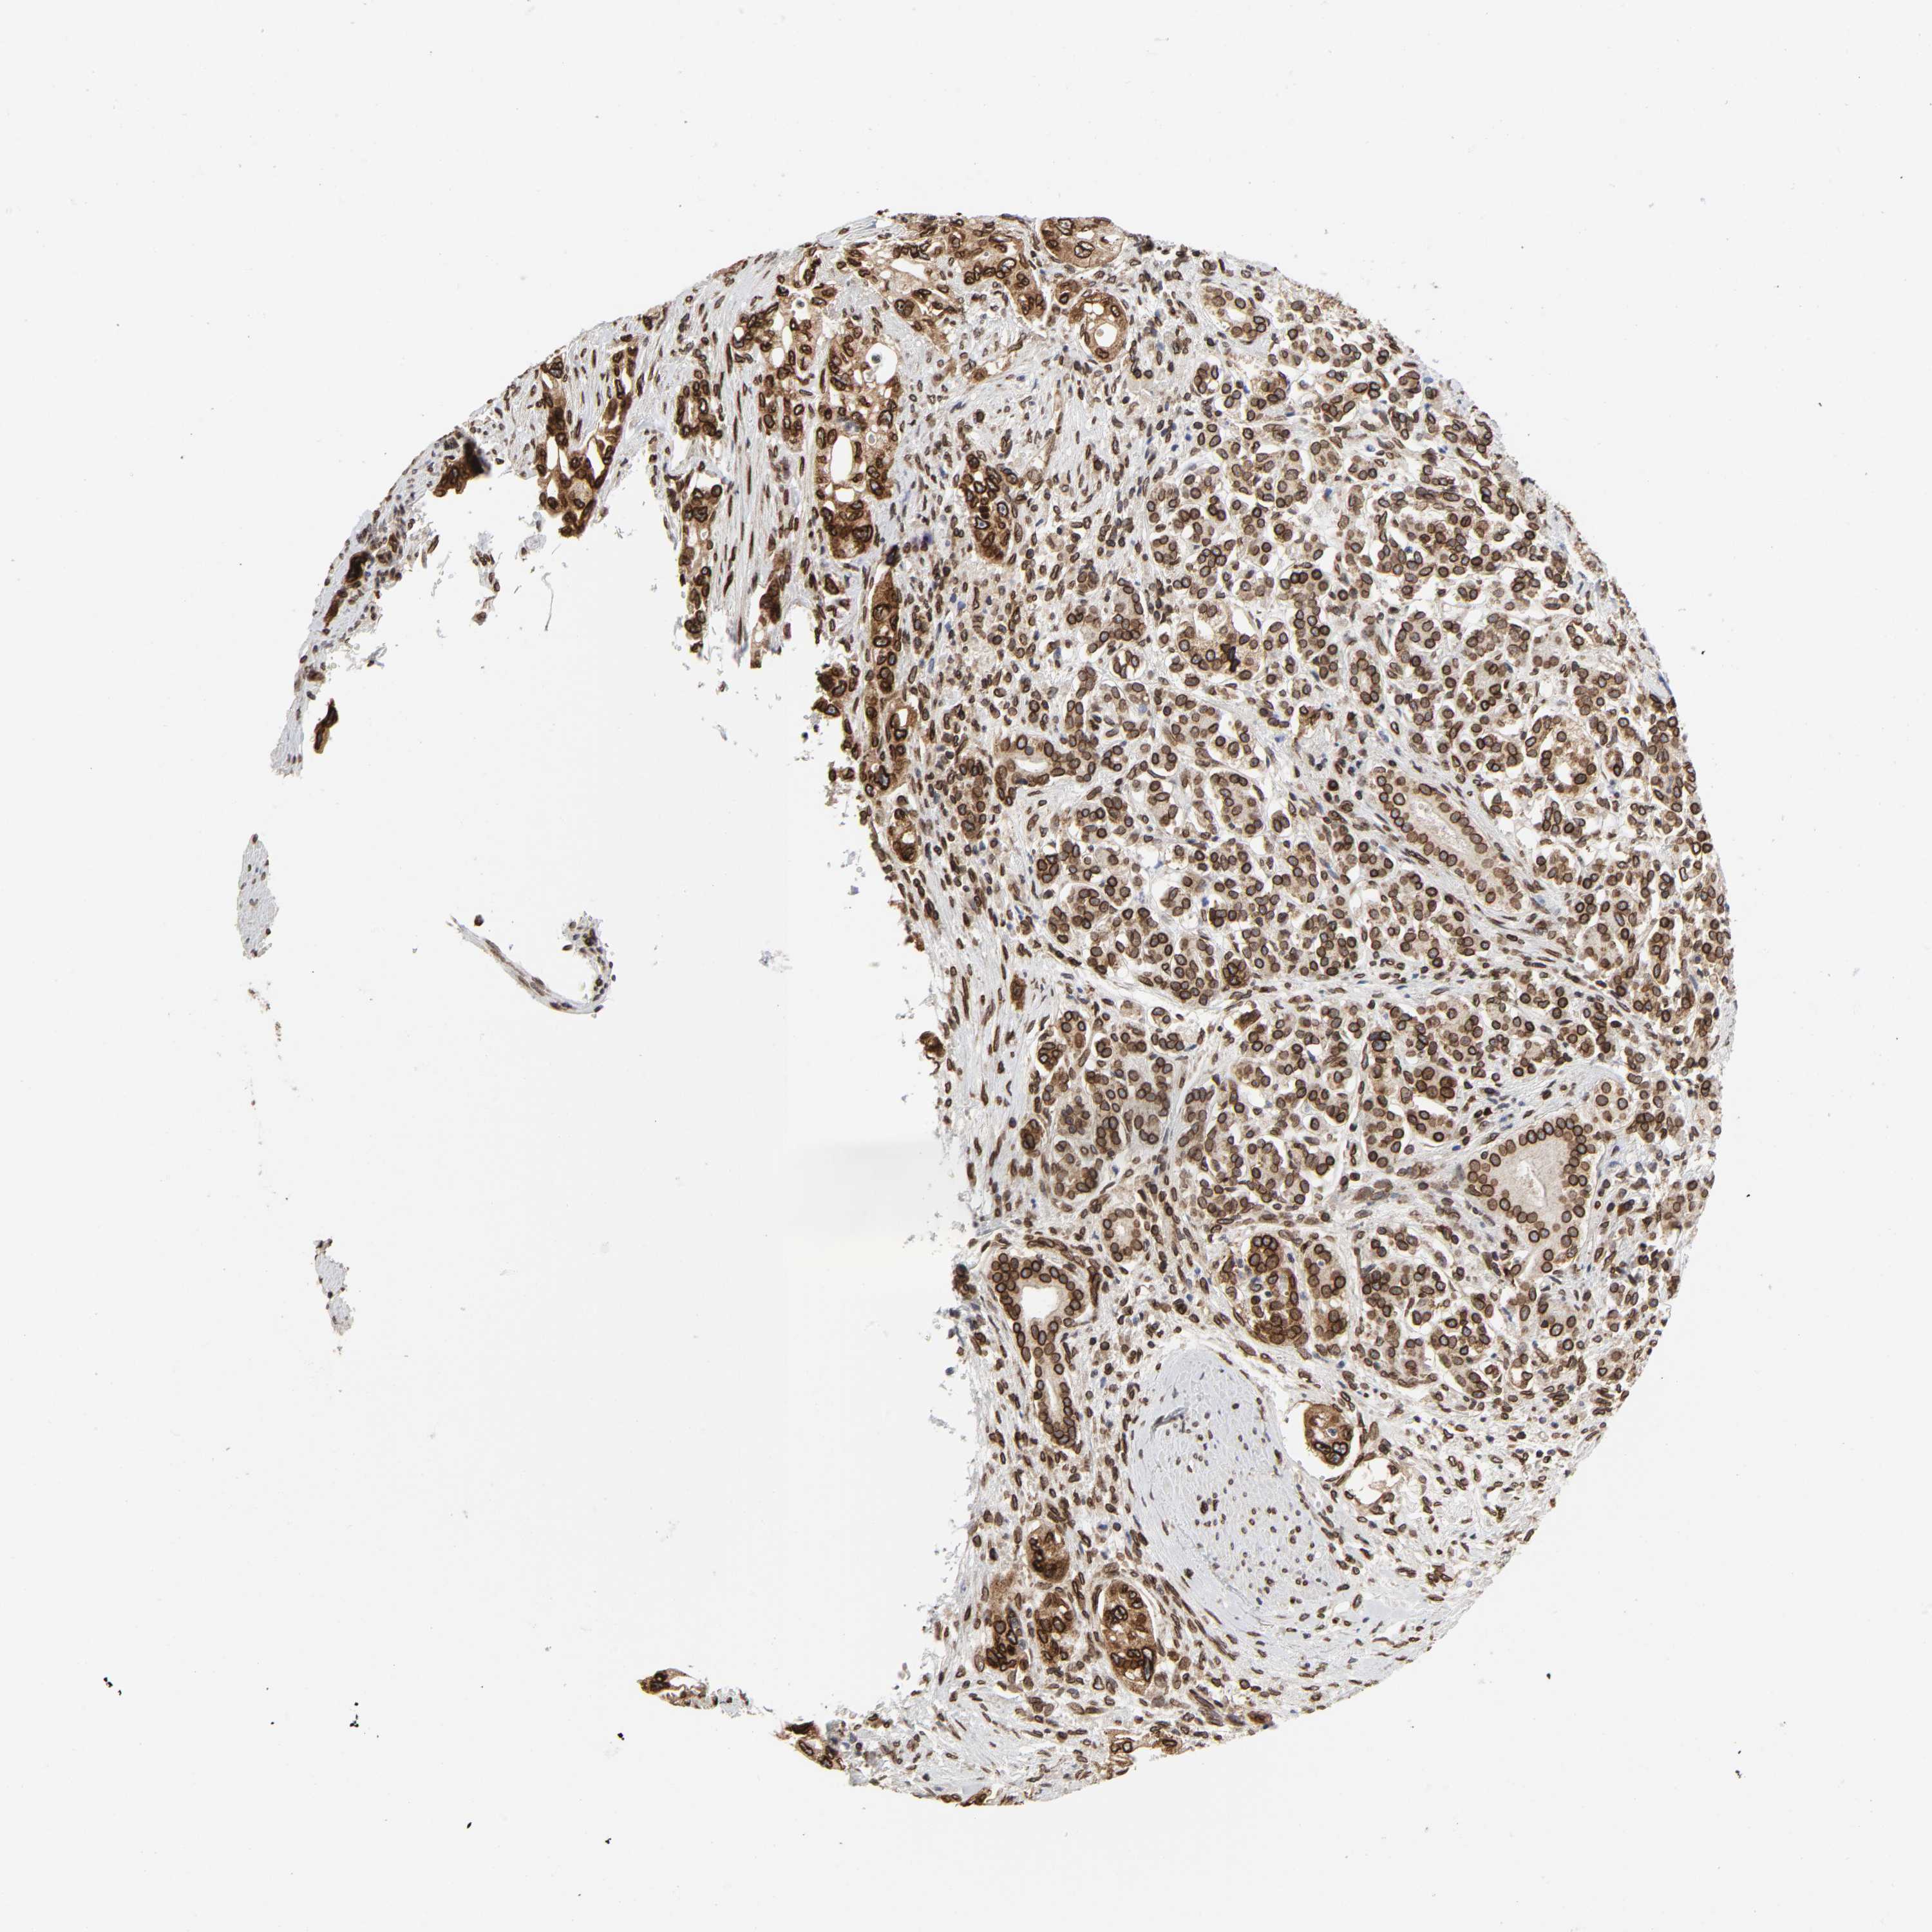

PANCREATIC CANCER - Protein expressioni

A mouse-over function shows sample information and annotation data. Click on an image to view it in a full screen mode. Samples can be filtered based on level of antibody staining by selecting one or several of the following categories: high, medium, low and not detected. The assay and annotation is described here.

Note that samples used for immunohistochemistry by the Human Protein Atlas do not correspond to samples in the TCGA dataset.

Antibody stainingi

Antibody staining in the annotated cell types in the current human tissue is reported as not detected, low, medium, or high, based on conventional immunohistochemistry profiling in selected tissues. This score is based on the combination of the staining intensity and fraction of stained cells.

Each image is clickable and will lead to virtual microscopy that enables deeper exploration of all samples and also displays staining intensity scores, fraction scores and subcellular localization as well as patient and tissue information for each sample.

Antibody HPA050110

Antibody CAB004293

Staining

High

Medium

Low

Not detected

Intensity

Strong

Moderate

Weak

Negative

Quantity

>75%

75%-25%

<25%

None

Location

Nuclear

Cytoplasmic/membranous

Cytoplasmic/membranous,nuclear

Adenocarcinoma, NOS